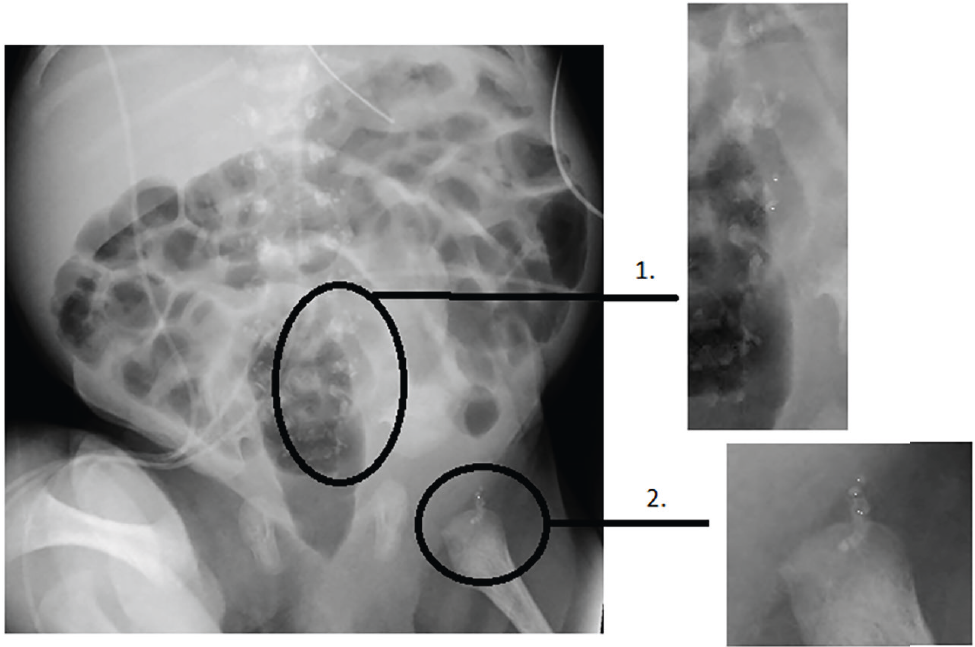

Elles confirment aussi la présence de calcifications multiples : trachéales, rachidiennes, du palais dur, du vomer, des cornets, du fémur. L’atteinte squelettique est ainsi évocatrice d’une forme sévère de chondrodysplasie ponctuée, c’est-à-dire une dysplasie osseuse congénitale caractérisée par la présence d’anomalies visibles sous forme de calcifications ponctuées au niveau des cartilages et visibles à la radiographie (Figure 1).

Figure 1 : Radiographie standard du patient – Chondrodysplasie ponctuée.

Figure 1: Standard X-ray of the patient – punctate chondrodysplasia.

1 : calcifi cations péri-vertébrales ; 2 : calcifi cations fémorales.